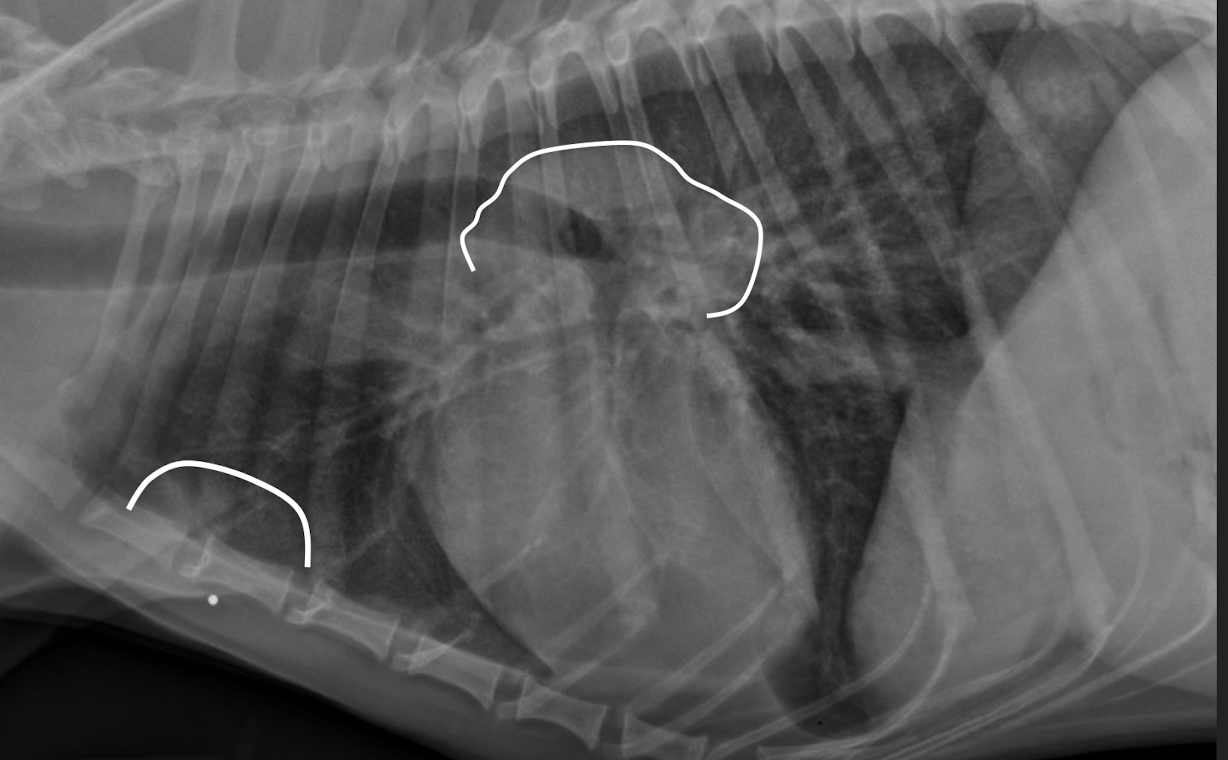

what kind of pattern?

intersitial and alveolar pneumonia